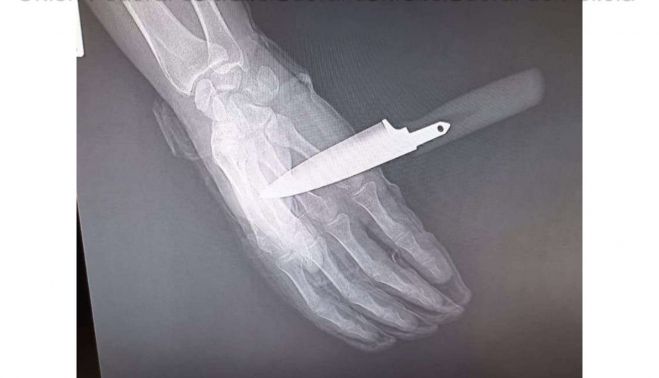

Tras el primer ataque, el agresor intentó asestar una segunda puñalada, que el agente consiguió repeler parcialmente, aunque la hoja del arma blanca le atravesó la mano. A pesar de la herida, el policía empleó su defensiva extensible y, con la colaboración de su compañera, logró reducir y detener al agresor, que fue trasladado posteriormente a dependencias policiales para su ingreso en los calabozos. El agente herido fue atendido en un centro hospitalario con el cuchillo aún clavado.